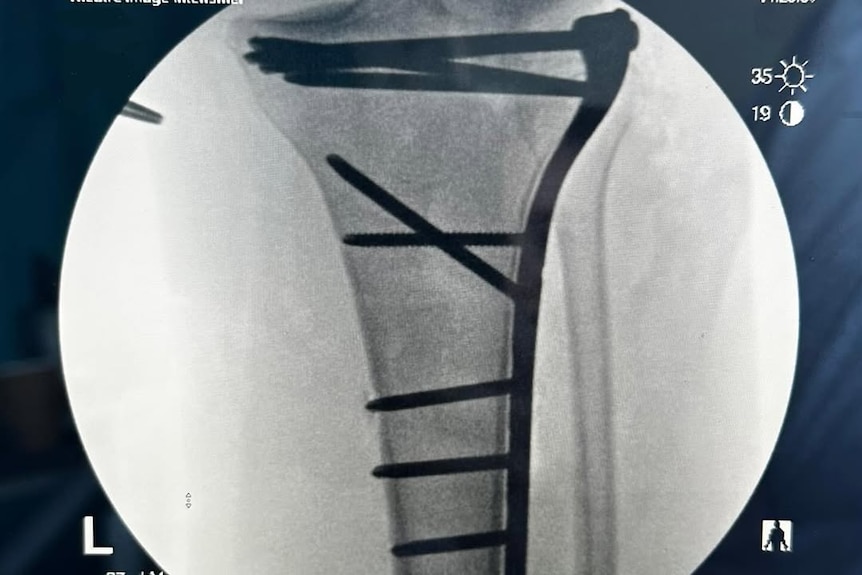

After two nights in Horsham, she was flown to The Alfred in Melbourne on the Tuesday, went under the knife to have plates and pins put in her knee the following day and was discharged two days later to start her rehabilitation journey.

Larcombe’s left tibia was broken up near her knee. (Supplied: Sarah Larcombe)